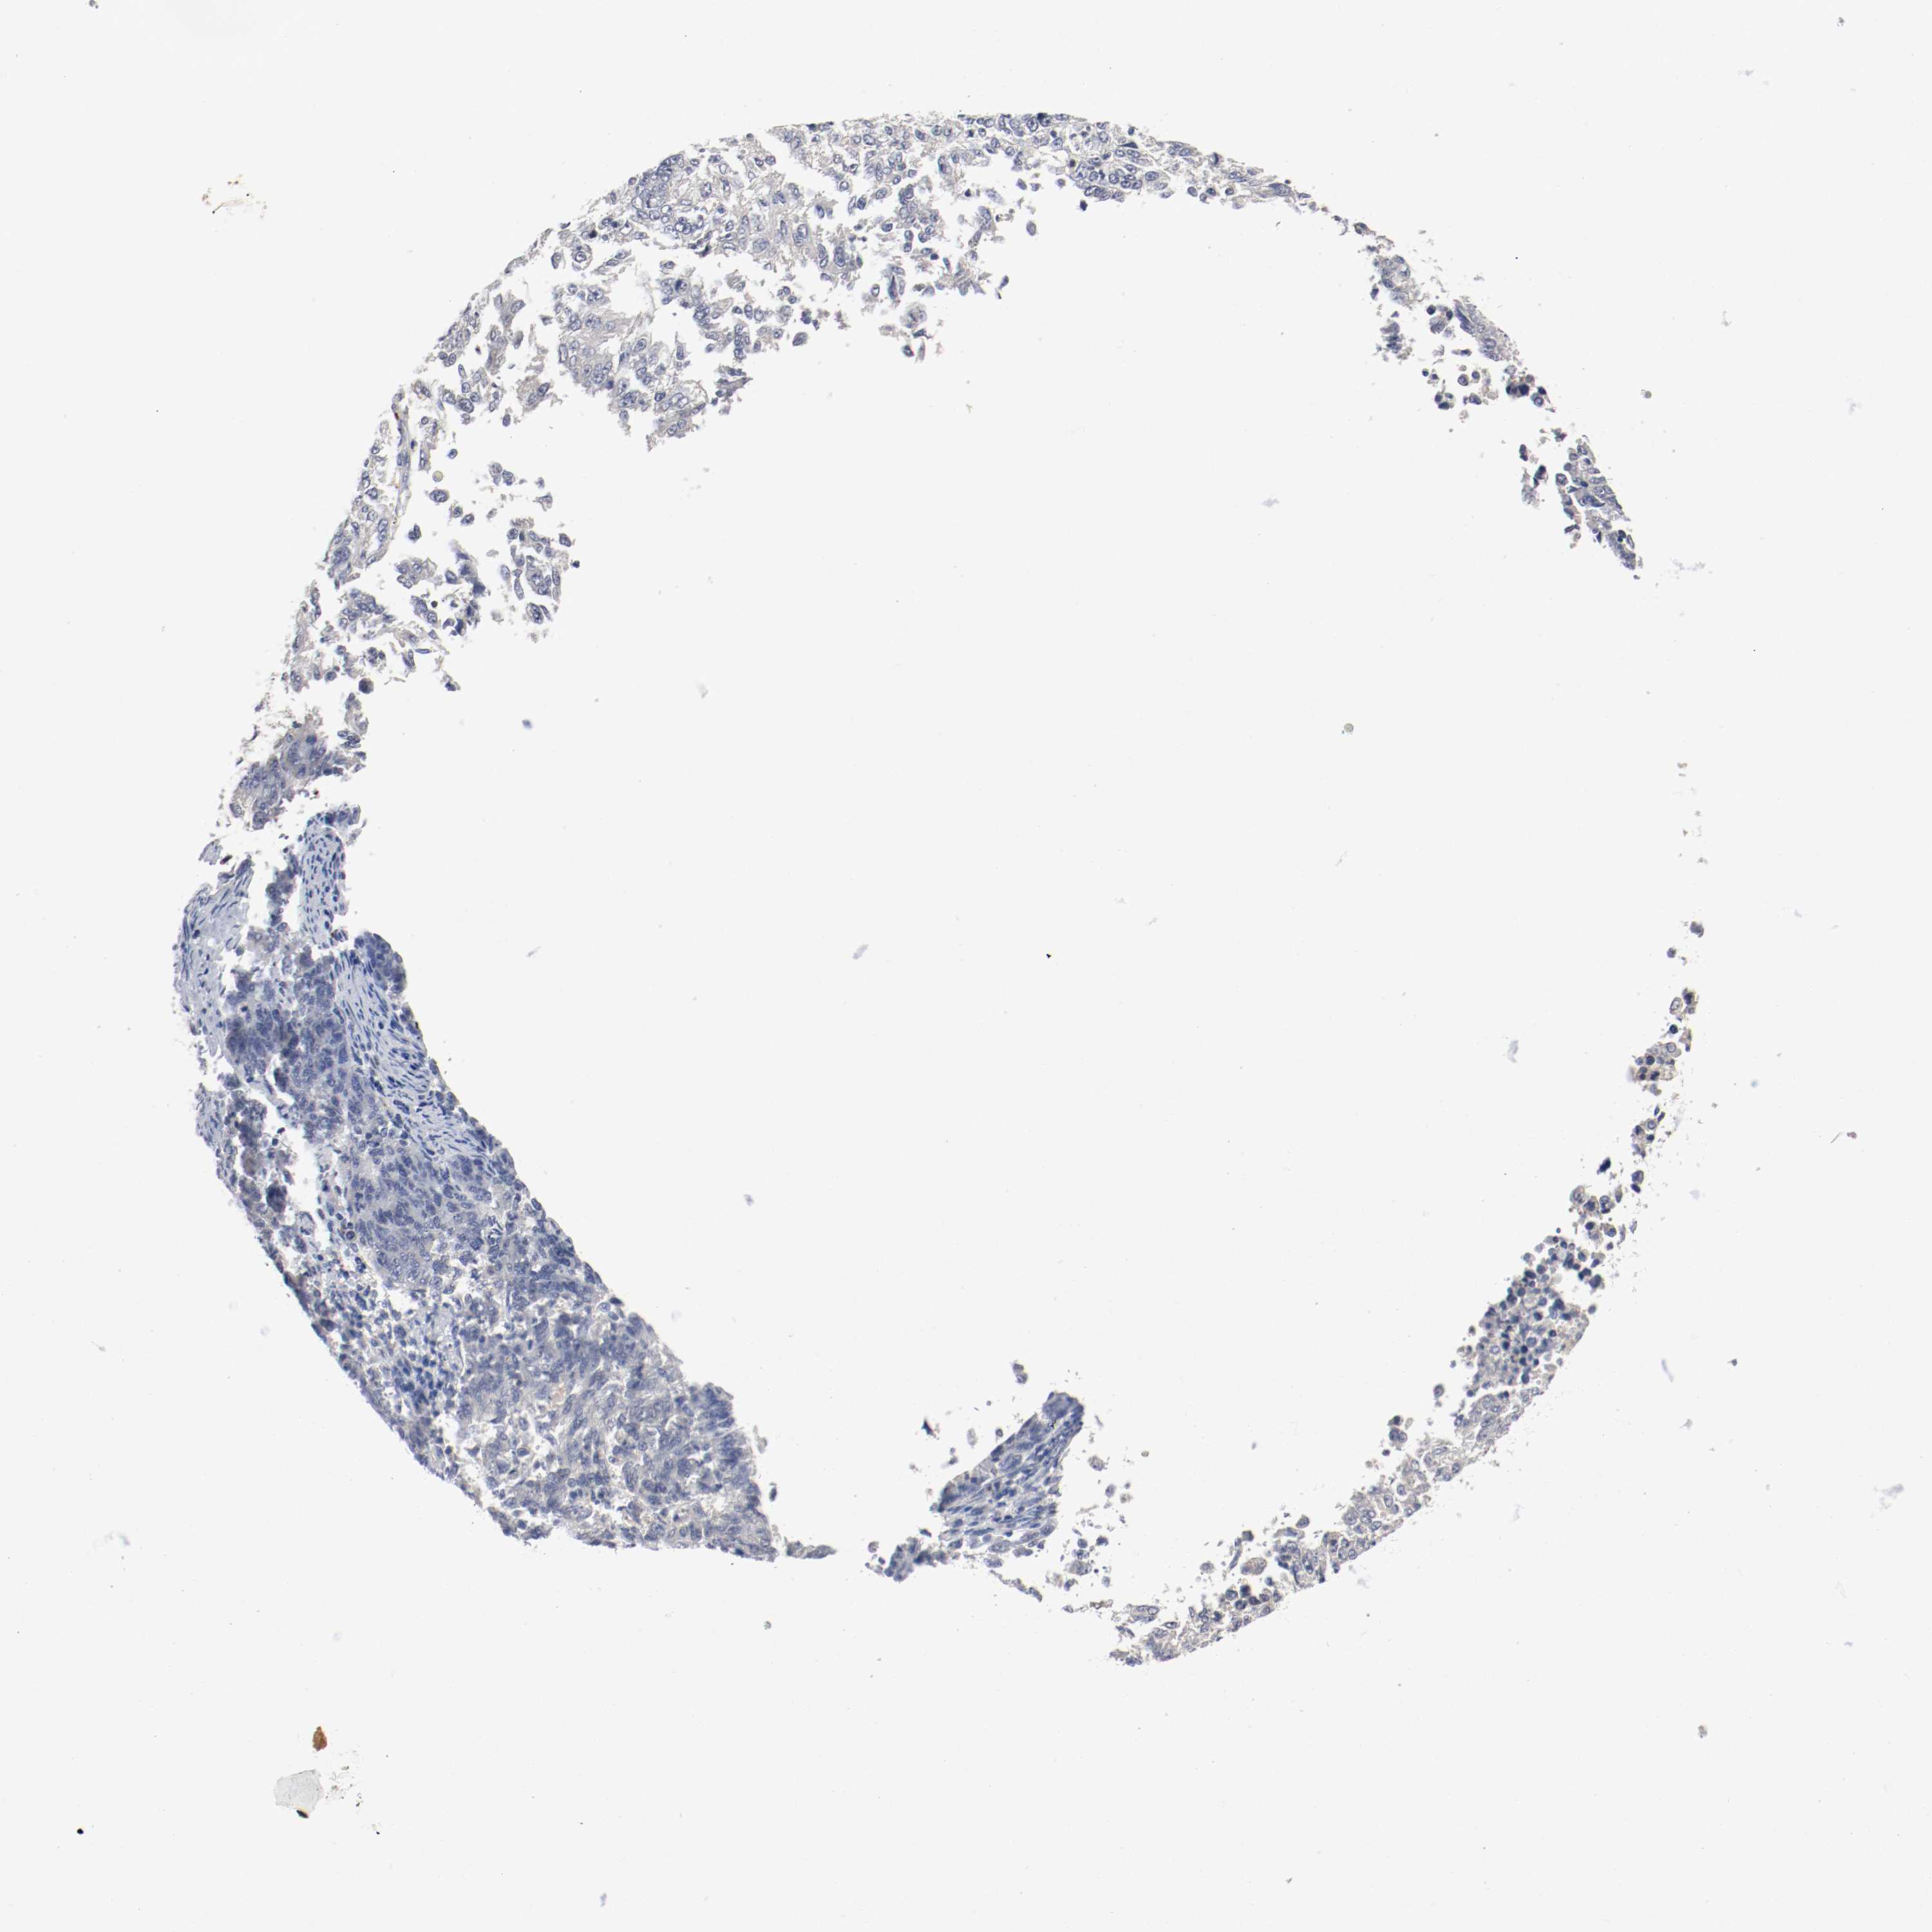

ENDOMETRIAL CANCER - Protein expressioni

A mouse-over function shows sample information and annotation data. Click on an image to view it in a full screen mode. Samples can be filtered based on level of antibody staining by selecting one or several of the following categories: high, medium, low and not detected. The assay and annotation is described here.

Note that samples used for immunohistochemistry by the Human Protein Atlas do not correspond to samples in the TCGA dataset.

Antibody stainingi

Antibody staining in the annotated cell types in the current human tissue is reported as not detected, low, medium, or high, based on conventional immunohistochemistry profiling in selected tissues. This score is based on the combination of the staining intensity and fraction of stained cells.

Each image is clickable and will lead to virtual microscopy that enables deeper exploration of all samples and also displays staining intensity scores, fraction scores and subcellular localization as well as patient and tissue information for each sample.

Antibody HPA005131

Staining

High

Medium

Low

Not detected

Intensity

Strong

Moderate

Weak

Negative

Quantity

>75%

75%-25%

<25%

None

Location

Nuclear

Cytoplasmic/membranous

Cytoplasmic/membranous,nuclear

Adenocarcinoma, NOS

Neoplasm, malignant, NOS